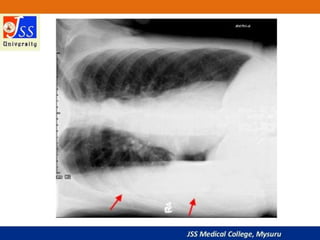

Chest X-rays are commonly used medical imaging tests that produce images of the structures and organs inside the chest such as the heart, lungs, blood vessels, and soft tissues. They can be used to diagnose conditions like pneumonia, lung cancer, and heart failure by detecting abnormalities in these structures. Chest X-rays expose patients to a very small dose of ionizing radiation but provide valuable medical information to guide diagnosis and treatment.